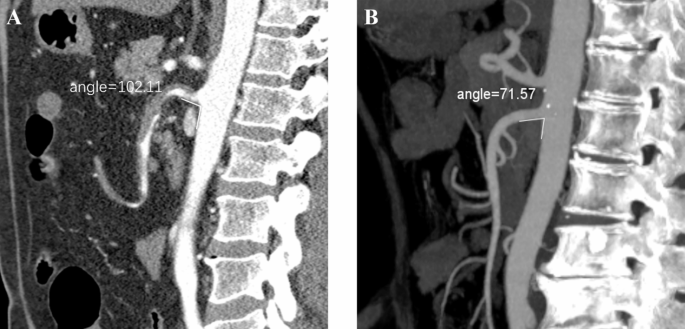

AMA was measured in the sagittal view of CTA. AMA was defined as the angle between the inferior SMA origin, a point 1 cm along the posterior wall of the SMA and a point 1 cm along the anterior wall of the distal aorta (Fig. 1)10,12. The diagnosis of SISMAD and measurement of the AMA was independently performed by two board-certificated radiologists blinded to the study purpose. A senior radiologist was consulted to reach a consensus when there was a disagreement between the two reviewers. Based on priorly measured AMA results, the patients were equally allocated into small, intermediate, and large angle levels, with 35 patients in each level.

The aortomesenteric angle was determined as the angle between the posterior wall of the superior mesenteric artery and the anterior wall of the distal aorta. (A) The aortomesenteric angle in one patient with SISMAD was 102.11 °. (B) The aortomesenteric angle in one patient without SISMAD was 71.57 °. SISMAD = spontaneous isolated superior mesenteric artery dissection